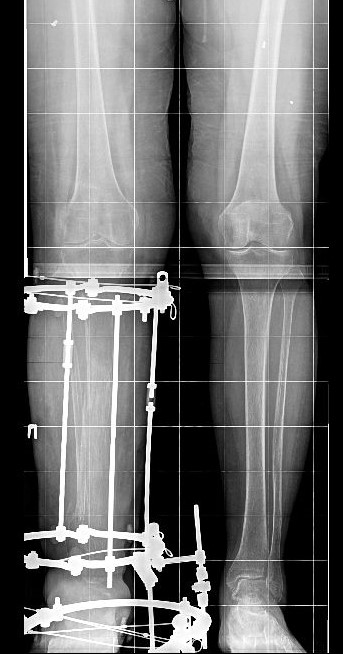

В Национальном медицинском исследовательском центре травматологии и ортопедии имени академика Г. А. Илизарова Минздрава России за лечение пациентки взялись врачи травматологи-ортопеды отделения №3 Клиники реконструктивной хирургии повреждений конечностей и таза. До лечения в Центре Илизарова пациентка уже перенесла 10 операций. Больше всего пострадала правая голень: обширные дефекты как мягких, так и костных структур.

«Мы выполнили реостеосинтез аппаратом Илизарова голени и стопы. Добиваемся полного сращения большеберцовой и таранной костей, чтобы получить артродез голеностопного сустава, минуя трофические проблемы», — рассказал суть оперативного лечения заведующий отделением №3 Центра Илизарова Виталий Нарицын.

После операции пациентка начала наступать на ногу и ходить. Врачи Центра Илизарова говорят, что в настоящее время костная ткань не готова к дальнейшей реконструкции, выраженный остеопороз настолько, что для проведения спиц не требуется силовое оборудование. Необходимо, чтобы пациентка начала активно ходить, в таком случае костная ткань обретет свою прочность и укрепит структуру.